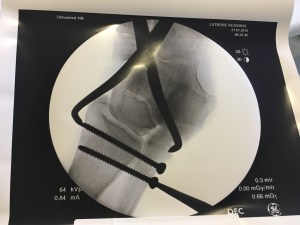

Taken during the surgery to ensure that the screws were in the right place. There was a second surgery, a couple of months later to remove them once the bone had healed.